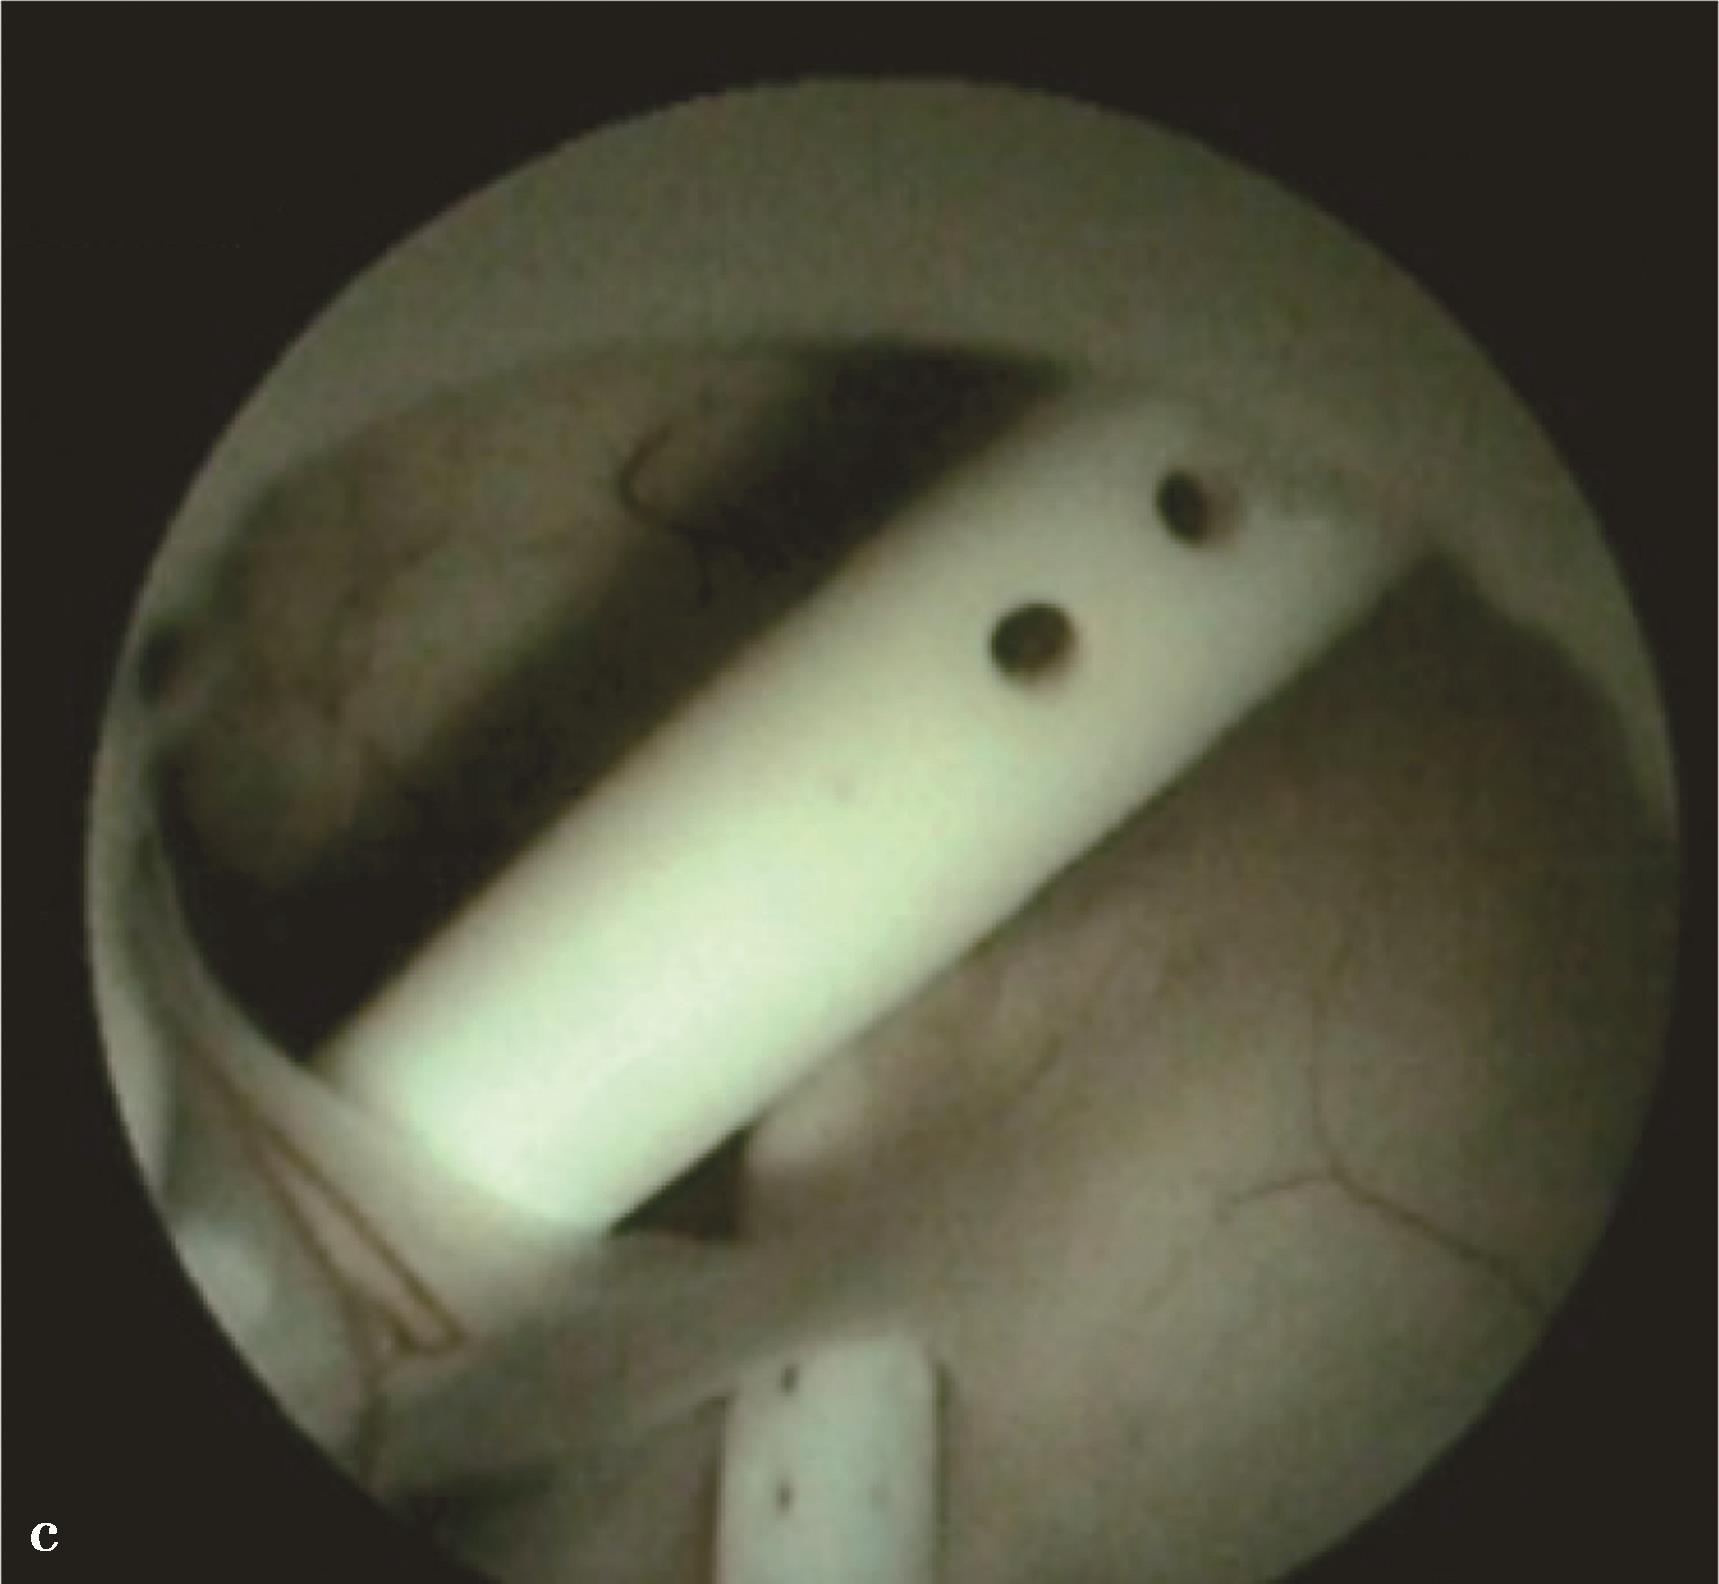

图3-1-2-5 导水管支架植入

图3-1-2-6 孤立第四脑室,内镜下见